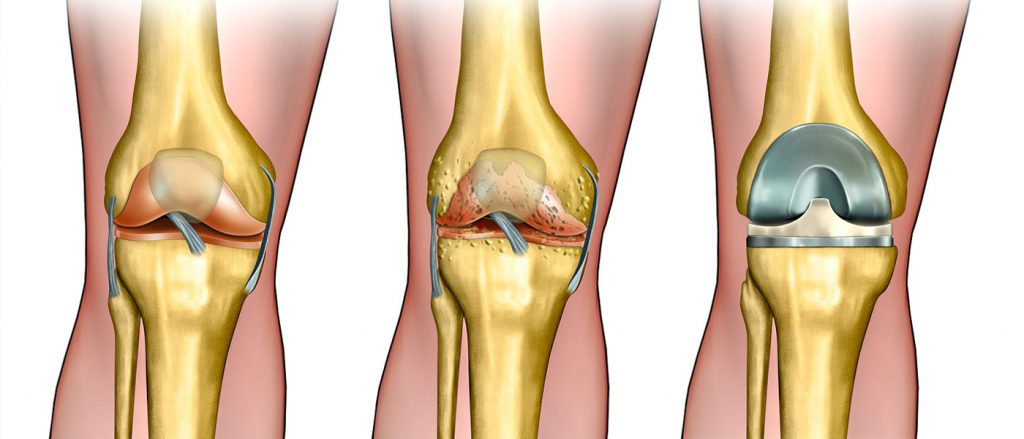

Hip fracture surgery is one of the treatment options available for those who have experienced a hip fracture. This procedure can be somewhat challenging, as it sometimes involves making an incision in the skin around the hip area to realign the broken bones. Despite the seriousness of a fracture in the hip area, recovery can take approximately four to six months. The treating orthopedic surgeon will determine the activities the patient should perform during this period.

The goal of hip fracture surgery is to treat the fractured joint or bone using one of two methods:

- Performing an open incision (surgical wound) in the affected area to realign the broken bones if they have shifted from their original position due to the injury.

Hip fracture surgery is considered a very important procedure, as it can cause serious disruptions in the patient’s daily life. Imaging techniques are used to determine the location of the fracture before treatment. Conservative (non-surgical) treatment can be followed in cases of stable injuries, helping to reduce pain until recovery is achieved.

Hip fracture surgery may seem challenging, but it is considered a suitable treatment option for fractures in the hip area. The patient should see a doctor immediately to determine the appropriate treatment method and realign the fractured bones to their natural position. This can be done through either an incision in the hip area or by inserting screws or metal plates. Patients can typically leave the hospital after about two weeks, and complete recovery may take from 3 to 6 months.

Does the Bone Return to Normal After a Fracture?

Hip fracture surgery can be scary for many people, and some may wonder if the bone returns to its normal state after the fracture. In reality, treating a hip fracture requires a surgical procedure, and the doctor may be able to realign the fractured bones after the break. This is done through a surgical procedure that involves proper fracture repair and stability of the bones using special plates. Therefore, hip fracture surgery should be performed under the supervision of a qualified surgeon after a comprehensive assessment of the case.